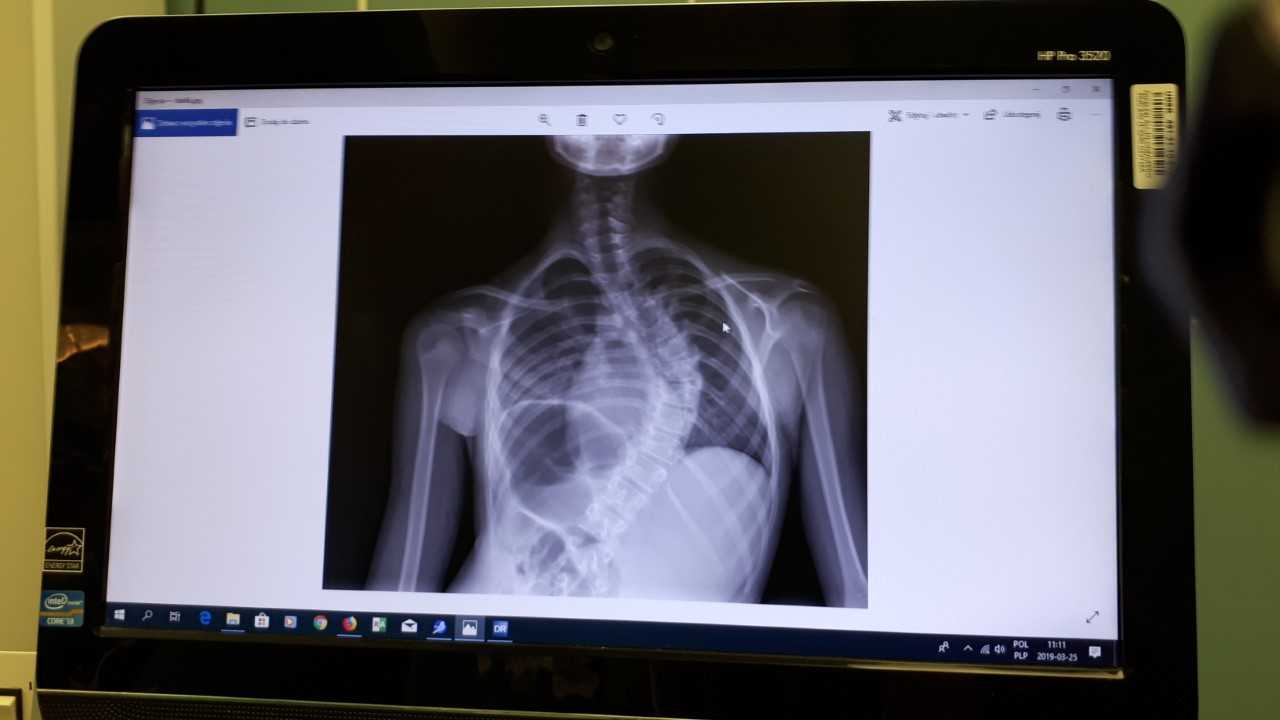

Pierwszą w Polsce operację bez usztywniania kręgosłupa u dziecka ze skoliozą przeprowadzono w poniedziałek (25.03) w Uniwersyteckim Dziecięcym Szpitalu Klinicznym w Białymstoku. Metoda ta pozwala w sześć tygodni wrócić pacjentowi do aktywności fizycznej.

Lekarze w Białymstoku przeprowadzili pierwszą w Polsce nowatorską operację skoliozy u dziecka, fot. Renata Reda

Operacji korekcji skoliozy idiopatycznej nowatorską techniką bez usztywniania kręgosłupa, tzw. VBT (ang. Vertebral Body Tethering), poddano 11-letnią dziewczynkę z Katowic. Operację przeprowadzili ortopedzi z Kliniki Ortopedii i Traumatologii Dziecięcej Uniwersytetu Medycznego w Białymstoku dr Paweł Grabala i dr Tomasz Guszczyn oraz światowej sławy chirurdzy kręgosłupa z USA dr Darryl Antonacci i prof. Randal Betz z Institute for Spine and Scoliosis (New Jersey) – poinformował Uniwersytet Medyczny w Białymstoku.

Innowacyjna metoda polega na wszczepieniu w kręgosłup ruchomych prętów elastycznych, bez usztywniania kręgosłupa. Dyrektor Uniwersyteckiego Dziecięcego Szpitala Klinicznego prof. Anna Wasilewska powiedziała, że to autorska metoda opracowana przez dr Antonacciego.

"Pręty umożliwiają dziecku powrót do normalnej aktywności w ciągu sześciu tygodni, nawet z gimnastyką artystyczną włącznie" – powiedziała Wasilewska. Dodała, że prof. Antonacci zaznacza także, że podczas takiej operacji nie jest wymagane – tak jak przy innych ortopedycznych – przetaczanie pacjentowi krwi.

Dr Antonacci poinformował, że takie operacje najlepiej przeprowadzać pacjentom w wieku 10-16 lat, choć brani są też pod uwagę pacjenci poniżej 10 lat i tzw. młodzi dorośli. Zaznaczył, że zabieg, ze względu na predyspozycje genetyczne, jest skuteczniejszy u dziewcząt niż u chłopców.

Dotychczas przeprowadzano operacje skolioz u dzieci, wszczepiając im tzw. pręty sztywne, które można było regulować pilotem sterującym. Dziecko z takimi prętami było jednak usztywnione, przy metodzie z prętami elastycznymi jest inaczej, pacjent nie jest usztywniony, elastycznych prętów nie trzeba też wymieniać. Prof. Antonacci wyjaśnił, że gdy elastyczne pręty ma wszczepione dziecko, które już przestało rosnąć, od razu ma prostowany kręgosłup, by zlikwidować skoliozę, a gdy pręty ma dziecko, które jeszcze rośnie, to kręgosłup prostuje się do wszczepionego pręta w trakcie wzrostu dziecka.